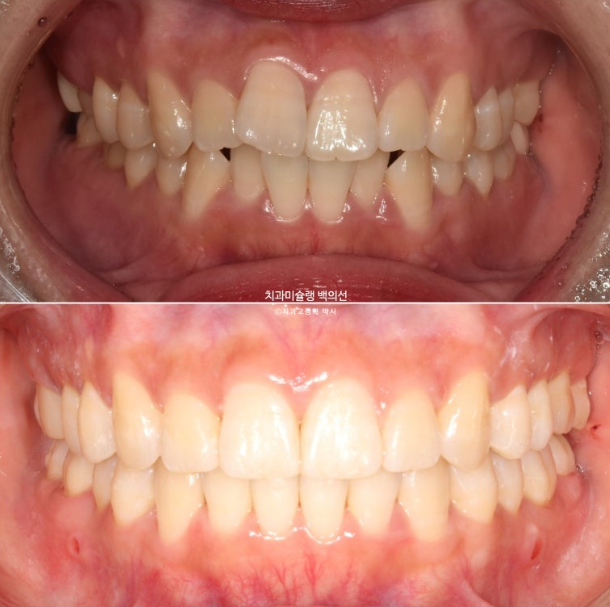

중심선은 잘 맞으나 앞니 사이 미세공간이 남아있습니다.

또한 위 앞니 사이 블랙트라이앵글도 눈에 띕니다.

발치공간은 깨끗하게 없어졌고

배열은 좋습니다.

중심선은 일치하고 교합도 좋습니다.

이제 전후비교 보겠습니다.

총 치료기간은 1년 10개월, 재제작은 2회 했습니다.

23.10~25.08